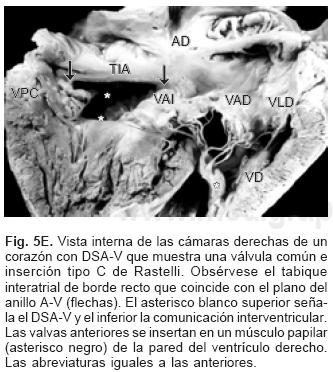

De los sesenta y cinco corazones con válvula común en veinticinco se determinaron los tipos de la clasificación de Rastelli que fueron los siguientes: en once (44%) las valvas anterosuperiores derecha e izquierda se insertaron a través de sus cuerdas tendinosas sobre la cresta del tabique ventricular y la CIV se ubicó en los espacios intercordales (tipo A de Rastelli) (Figs. 1A y 5A). En un espécimen las valvas anterosu–periores izquierda (valva puente) y derecha se insertaron sobre la cara derecha del tabique ventricular por debajo de su cresta (Fig. 5B) y en otro dicha inserción se hizo en la parte superior del cuerpo de la trabécula septomarginal (Fig. 5C). En ocho corazones (32%) la inserción de esas valvas se estableció en un músculo papilar situado en la unión del tabique ventricular con la pared libre del ventrículo derecho y la valva anterosuperior izquierda pasó como puente por encima de la CIV (tipo B de Rastelli) (Figs. 1B y 5D) y en seis corazones (24%) la inserción de las valvas anterosuperior izquierda (valva puente) y derecha se insertaron en un músculo papilar de la pared libre del ventrículo derecho y esta valva se ubicó por encima de la CIV (tipo C de Rastelli) (Figs. 1C y 5E). En los cuarenta corazones restantes no fue posible determinar los tipos de Rastelli debido a que treinta y tres de ellos presentaron doble entrada ventricular (Fig. 6A) dos tuvieron modificaciones anatómicas generadas por la cirugía y cinco por presentar mutilaciones realizadas durante la necropsia. Los cinco especímenes con dos válvulas separadas tuvieron estructura trifoliada dentro de la unión A–V común (Figs. 3B y 6B); la válvula A–V izquierda mostró una valva lateral y dos septales anterior y posterior unidas a la cresta del tabique ventricular, lo que obliteró la CIV (Fig. 6C). La válvula A–V derecha mostró una valva septal displásica, una anterior y una posterior (Figs. 3B y 6B).

Se ha postulado que el defecto septal A–V es consecuencia de la falta de desarrollo y fusión de las almohadillas endocárdicas A–V dorsal y ventral, proceso anómalo que explica todas las alteraciones anatómicas presentes en esta cardiopatía.1,21 En vez de formarse dos anillos fibrosos como ocurre en el corazón normal se constituye uno común, dentro de él se forman dos válvulas A–V separadas o una válvula A–V común, lo que ha servido de base para la clasificación de esta cardiopatía congénita.2–4 Ambas formas tienen las mismas características patológicas básicas. Las dos válvulas separadas son de estructura trifoliada, la izquierda presenta 2 valvas septales anterior y posterior y una lateral, las valvas septales están separadas por una comisura que en el pasado se consideró erróneamente como una hendidura que según su extensión puede provocar insuficiencia valvular.23 Este concepto surgió debido a que la válvula A–V izquierda de esta cardiopatía se consideró homóloga de la válvula mitral del corazón normal, en realidad ambas son análogas, es decir cumplen una función similar pero tienen orígenes diferentes; ya se mencionó que en el corazón normal la valva medial de la válvula mitral deriva preponderantemente del componente izquierdo del tabique A–V doblado mientras que en esta cardiopatía la válvula A–V izquierda se origina de un nivel más inferior a partir del mesénquima que circunda el canal A–V común. En rigor en esta cardiopatía la válvula A–V izquierda no debe llamarse mitral, ya que su constitución es trifoliada, por lo que es preferible denominarla válvula A–V izquierda; las valvas septales de ésta se unen de manera continua a la cresta del tabique ventricular, con lo que queda obliterada la CIV perimembranosa y de entrada. Este hecho es determinante del establecimiento del cortocircuito por encima de las valvas A–V; el espacio entre éstas y el borde inferior del tabique interatrial comúnmente se ha considerado como FP, que en realidad es la suma del DSA–V y del FP; cuando éste está presente el borde inferior del tabique interatrial es cóncavo y queda por encima del plano del anillo fibroso A–V. Se han descrito casos en que dicho borde inferior no es cóncavo sino recto y coincide con el plano A–V, situación en la que está ausente el FP y el cortocircuito interatrial se establece a nivel del defecto septal A–V.2,9 Cuando se desarrolla una válvula A–V común con su patrón de cinco valvas, la gran comunicación permanece permeable.1,2,16,21